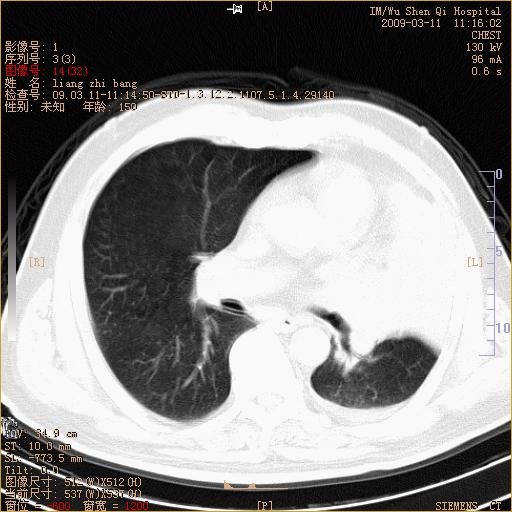

标题: CT18604:男,60岁,咳嗽一月余 [打印本页]

标题: CT18604:男,60岁,咳嗽一月余

1)考虑左肺上叶中央型肺癌并左肺上叶肺不张;建议必要时行纤支镜检查进一步明确诊断。2)左侧胸腔积液。

肺门肿块、支气管开口闭塞伴肺不张及胸水!典型的中心型肺癌变现!

1、左肺上叶中央型肺癌并上叶阻塞性肺不张。

2、左侧胸腔少量积液,右侧胸膜轻度增厚。

左肺们肿块并左肺上叶不张。考虑左肺中心性肺癌并左肺上叶不张及左侧胸腔积液